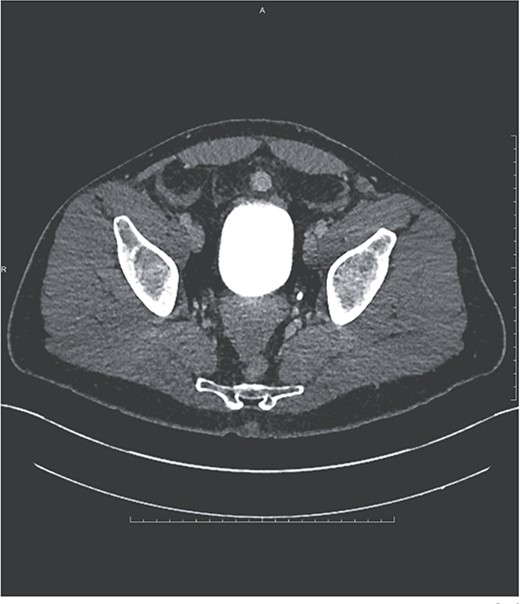

A 35-year-old male presented to the emergency department with a 1-day history of worsening left abdominal pain after reported consumption of psilocybin mushrooms. The patient denied any other inciting events or trauma. He had a history of an exploratory laparotomy and splenectomy at 12 years of age due to a traumatic sports injury and was incidentally diagnosed with splenosis in his left abdomen and pelvis at an outside hospital during a workup for abdominal pain 6 years prior to presentation. Examination revealed tenderness in the left hemiabdomen with guarding as well as hemodynamics within the normal range. Point-of-care ultrasound demonstrated fluid in Morrison’s pouch as well as a large volume of fluid in the pelvis. A computed tomography (CT) scan with IV contrast showed a large amorphous 17-cm mass-like structure in the mesentery of his left hemiabdomen consistent with a hematoma, and a multilobulated heterogeneously enhancing lesion within the lateral aspect of this hematoma. Also noted was active extravasation at the lateral aspect of the mass, arising from a vessel that appeared to be a terminal branch of the main splenic artery but that terminated into the mass within the left abdomen/pelvis (Fig. 1).

Coronal and axial views of CTA images of the abdomen and pelvis reveal a multilobulated heterogenous mass measuring 16.7 × 6.9 × 8.3 cm in the left mid-abdomen. Curvilinear foci of enhancement are visualized at its lateral aspect, originating from a prominent arterial vessel extending from the splenic artery.